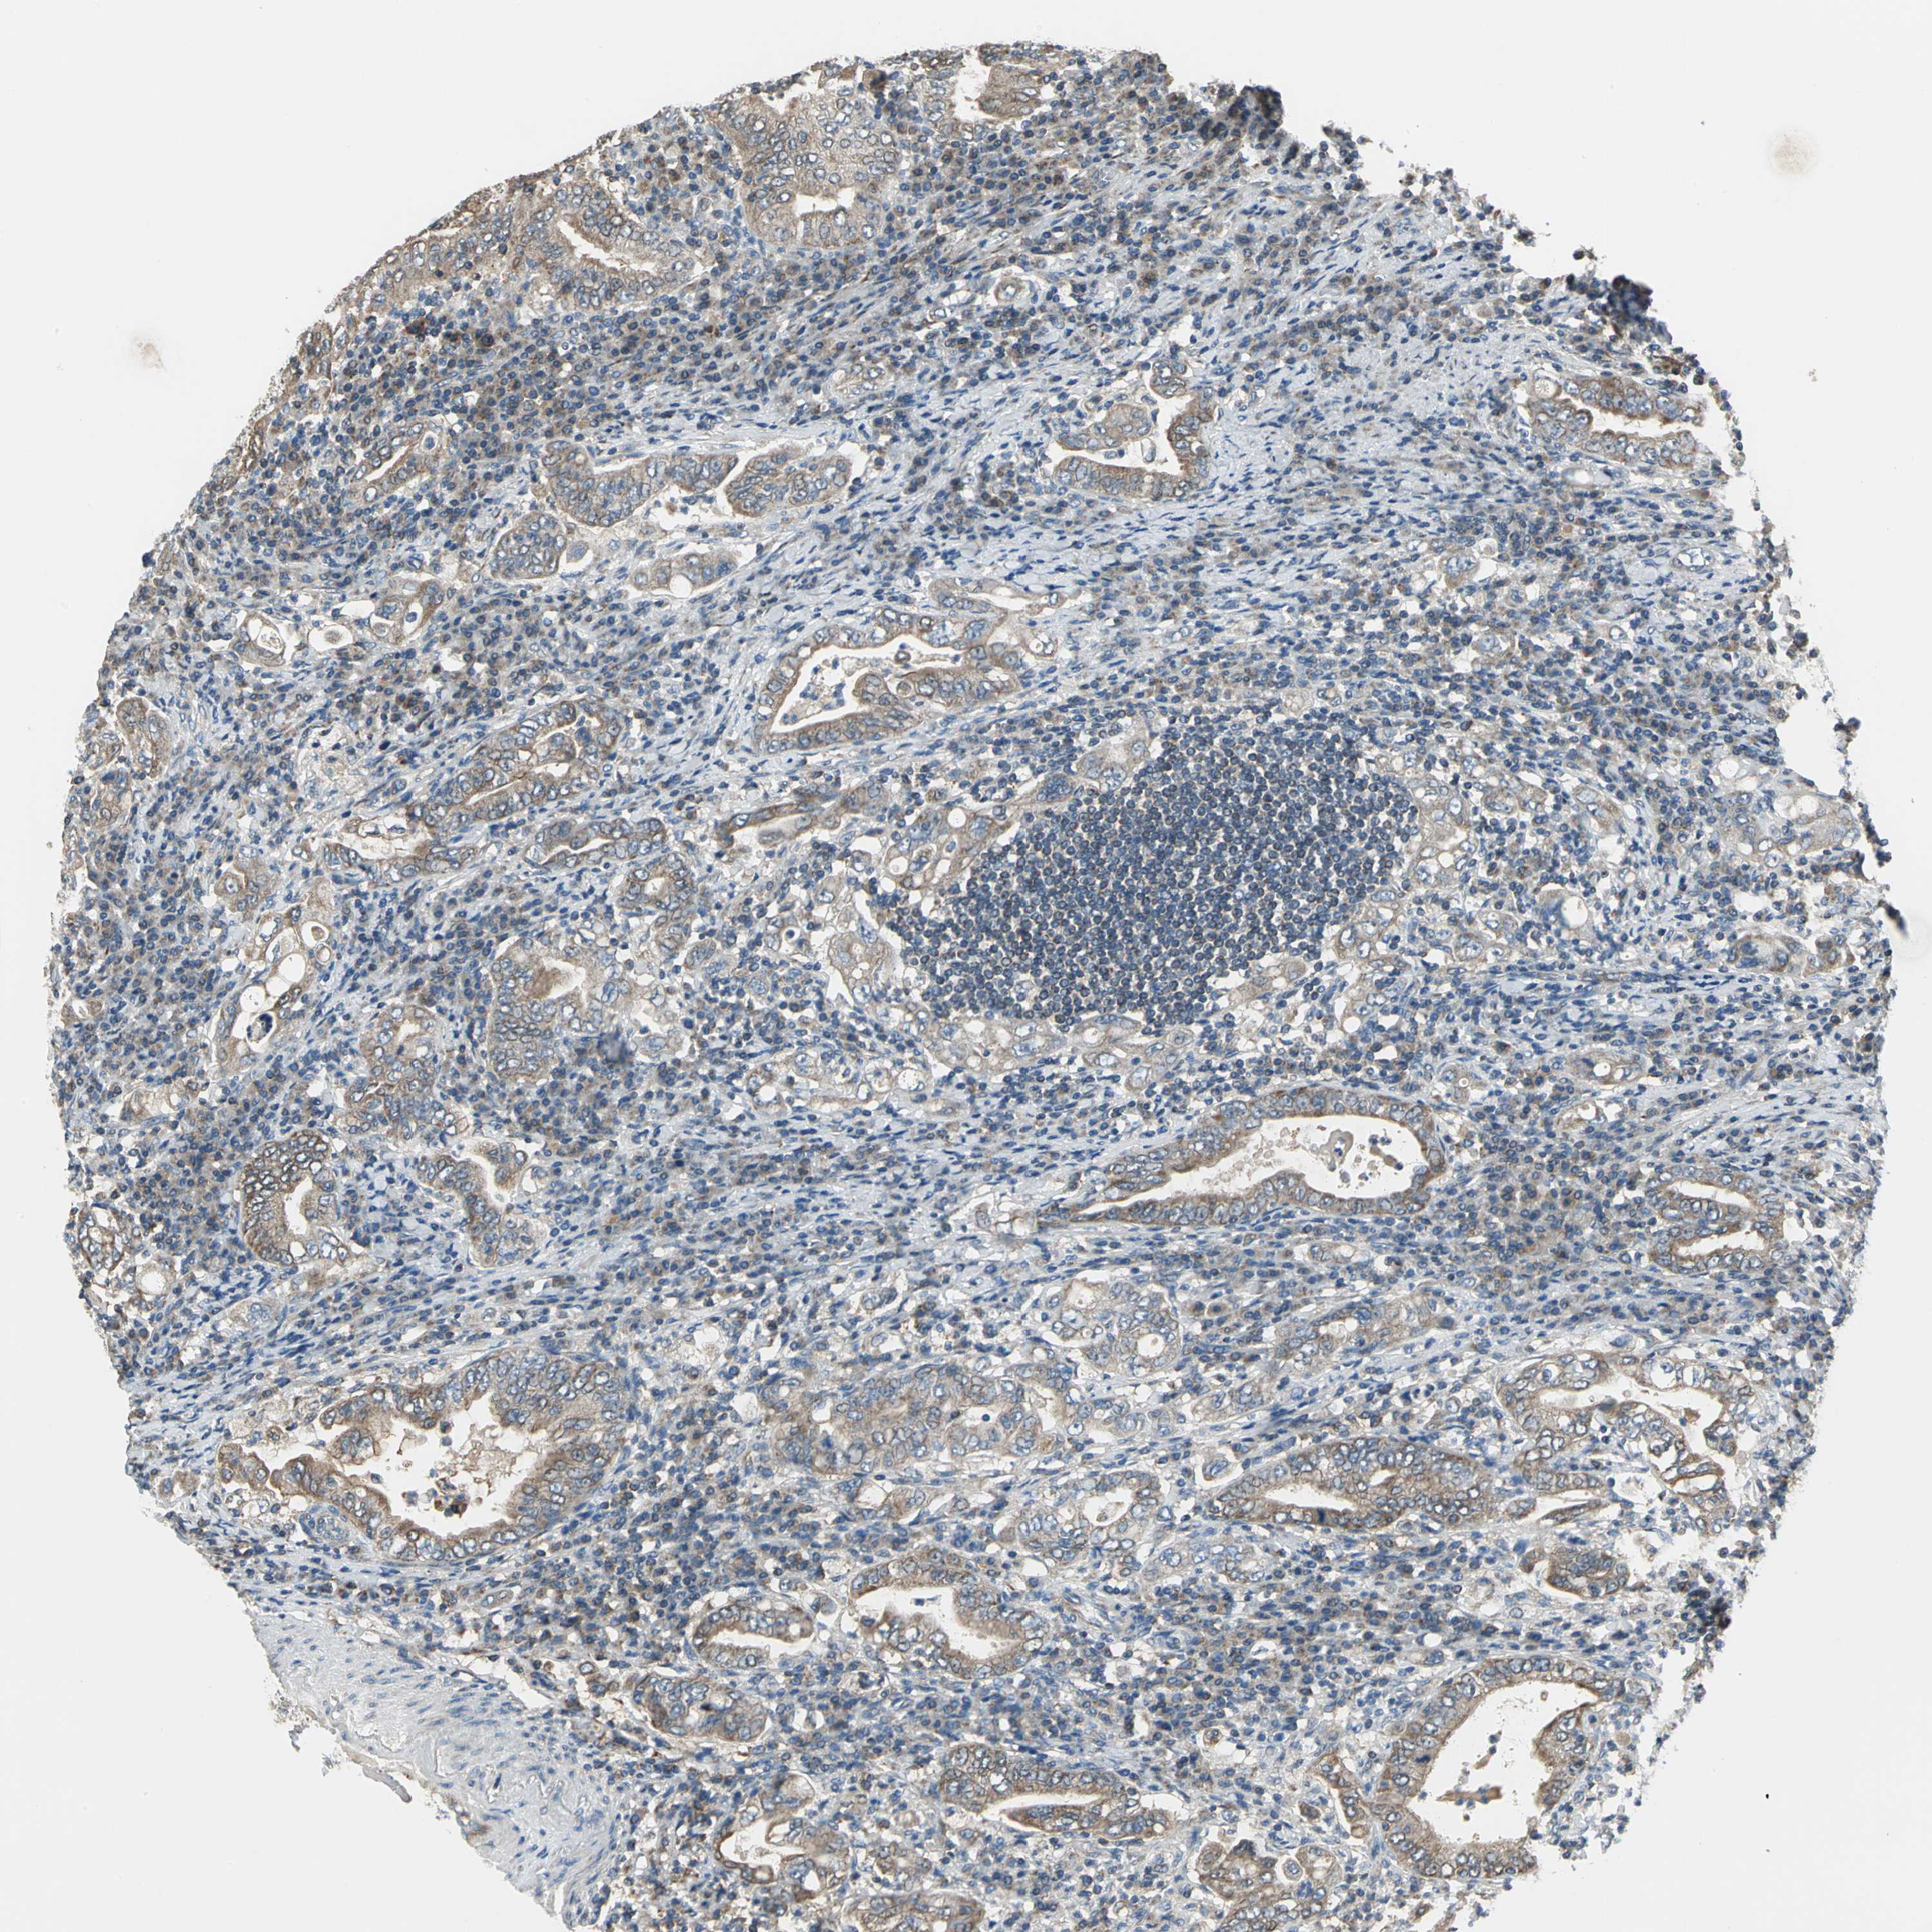

STOMACH CANCER - Protein expressioni

A mouse-over function shows sample information and annotation data. Click on an image to view it in a full screen mode. Samples can be filtered based on level of antibody staining by selecting one or several of the following categories: high, medium, low and not detected. The assay and annotation is described here.

Note that samples used for immunohistochemistry by the Human Protein Atlas do not correspond to samples in the TCGA dataset.

Antibody stainingi

Antibody staining in the annotated cell types in the current human tissue is reported as not detected, low, medium, or high, based on conventional immunohistochemistry profiling in selected tissues. This score is based on the combination of the staining intensity and fraction of stained cells.

Each image is clickable and will lead to virtual microscopy that enables deeper exploration of all samples and also displays staining intensity scores, fraction scores and subcellular localization as well as patient and tissue information for each sample.

Antibody HPA005853

Staining

High

Medium

Low

Not detected

Intensity

Strong

Moderate

Weak

Negative

Quantity

>75%

75%-25%

<25%

None

Location

Nuclear

Cytoplasmic/membranous

Cytoplasmic/membranous,nuclear

Adenocarcinoma, NOS

Adenocarcinoma, High grade